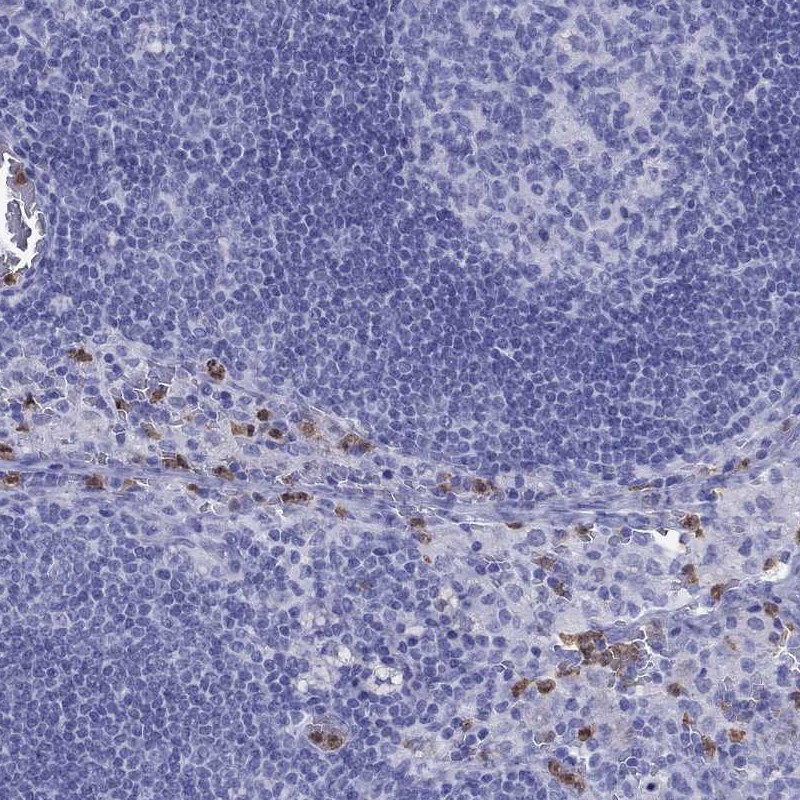

Immunohistochemistry analysis in human lymph node and testis tissues using Anti-SLAMF1 antibody. Corresponding SLAMF1 RNA-seq data are presented for the same tissues.